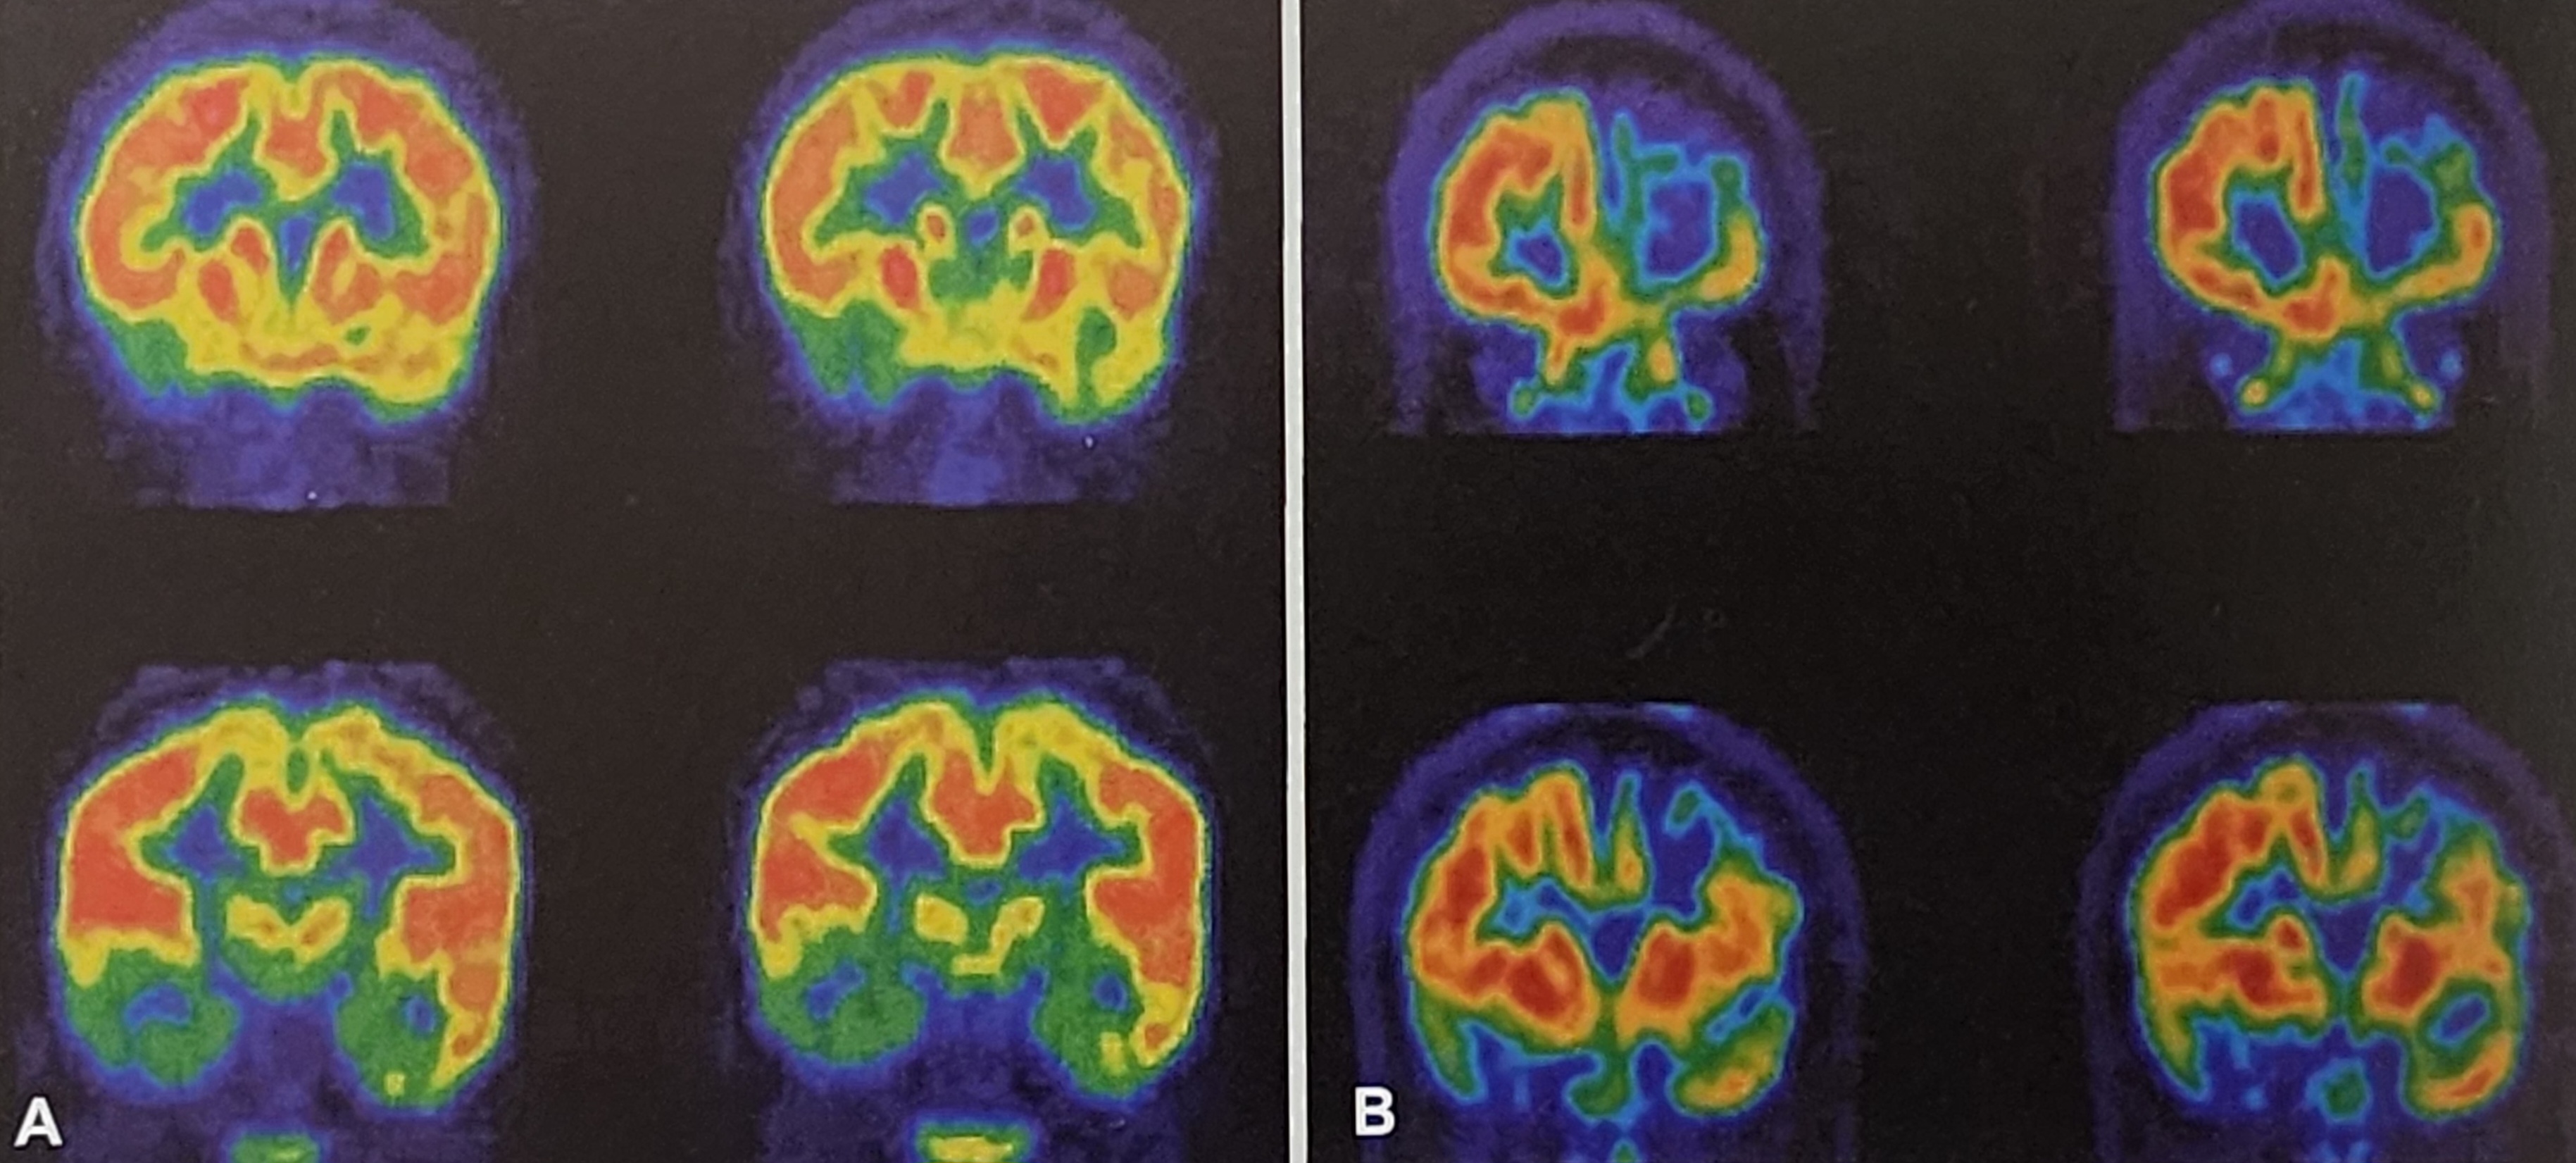

(2) 양전자 방출 단층촬영(PET, Positron Emission Tomography)

PET 검사는 뇌의 대사 활동을 평가하는 검사로, 뇌전증 발생 부위가 정상적인 뇌보다 포도당 대사가 감소하는 특징을 보이는 것을 이용한다.

- 18F-FDG PET은 가장 일반적으로 사용되는 방법으로, 뇌의 대사 저하 부위를 평가하는 데 도움을 준다.

- MRI에서 뚜렷한 병변이 보이지 않을 때 PET 검사를 활용하면 피질이형성 같은 미세한 병변을 찾아낼 수 있다.